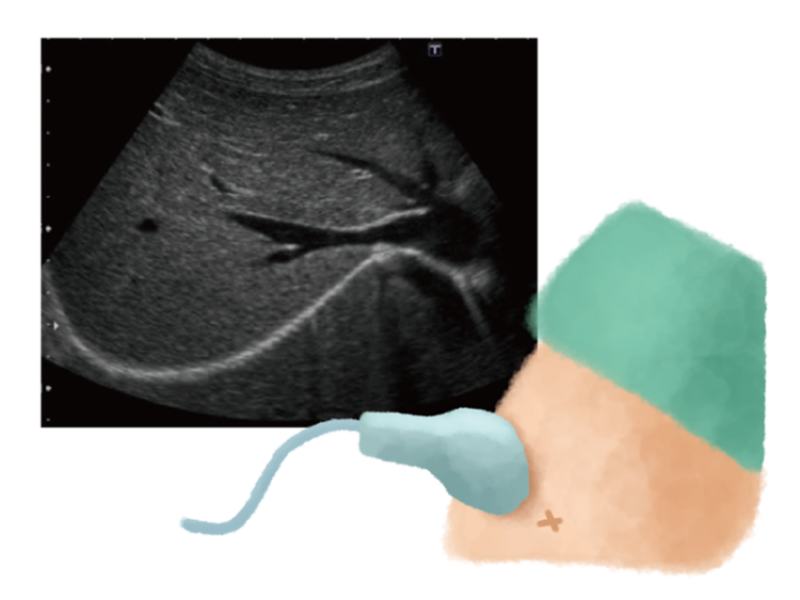

・Abdominal Ultrasound (Echo) Examination: An ultrasound is a highly effective, painless, and safe way to visually confirm the degree of fat accumulation in the liver (severity of fatty liver), abnormalities in the liver’s shape and size, and signs of liver fibrosis (stiffness). It is not uncommon to find fatty liver via an ultrasound even if blood test values are within the normal range. The director of our clinic is a liver disease specialist certified by the Japan Society of Hepatology, as well as an ultrasound specialist, providing high-quality examinations to ensure that even the slightest changes are not overlooked.